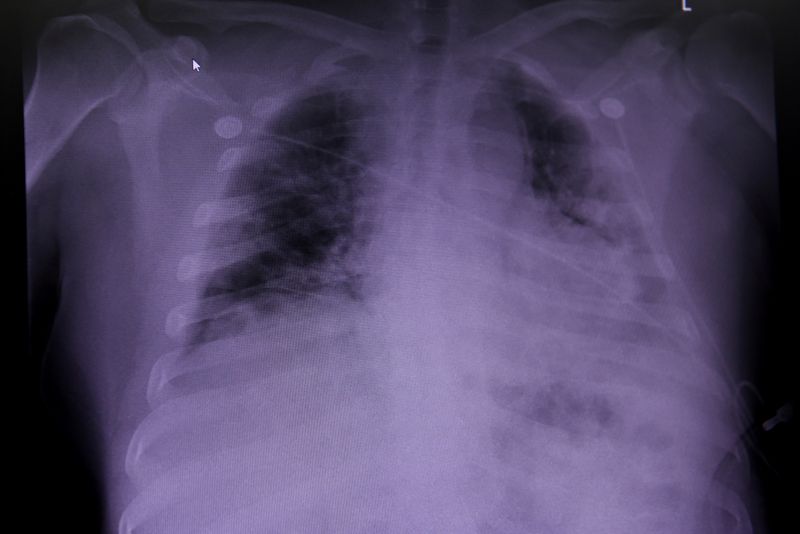

Jcubail meyajnáal, Bruno Rodríguez Parrilla, tu tsikbaltaj le domingo máanika’, u registroil sanitario tu noj lu’umil Bielorrusia, tu’ux yaan Cimavax, u yáax báakunail terapeutikail ti’al u ts’unusil, wa cáncer, tu sot’ot, wa pulmón, wíinik ku beeta’al te’el peteno’.

‘U báakunail Cimavaxe’ tu k’amaj u sanitarioil chíimpolal tu noj lu’umil Bielorrusia. Biotecnológico yéetel farmacéutico meyaj ku beeta’al Cubae’ láayli’ u yantal u yich, kex tumen yaan talamilo’ob ku máansik ikil u jach k’áatal u beel tumen Estados Unidos”, a’alab tumen noj lu’um tu kúuchil X.

Le 12 ti’ julio máanika’, u kúuchil Centro Pericial y de Pruebas en Atención Sanitaria, ti’ u mola’ayil Ministerio de Salud ti’ europeoil noj lu’ume’, tu k’ubaj u registroil Cimavax, báakuna beeta’ab tumen u kúuchil Centro de Inmunología Molecular de la isla.

Le je’ela’ leti’e’ yáax registrarta’an de oficial ichil tuláakal yóok’ol kaab, ti’al u ts’aatáanta’al u ts’unusil sot’ot. U ts’unusil sot’ote’ leti’e’ ba’ax kíinsik, tu jach ya’abil, xiibo’ob yéetel ko’olel, tumen óoli’ ku chíimbesik kex u 25 por cientoil máak ku kíimil tumen.